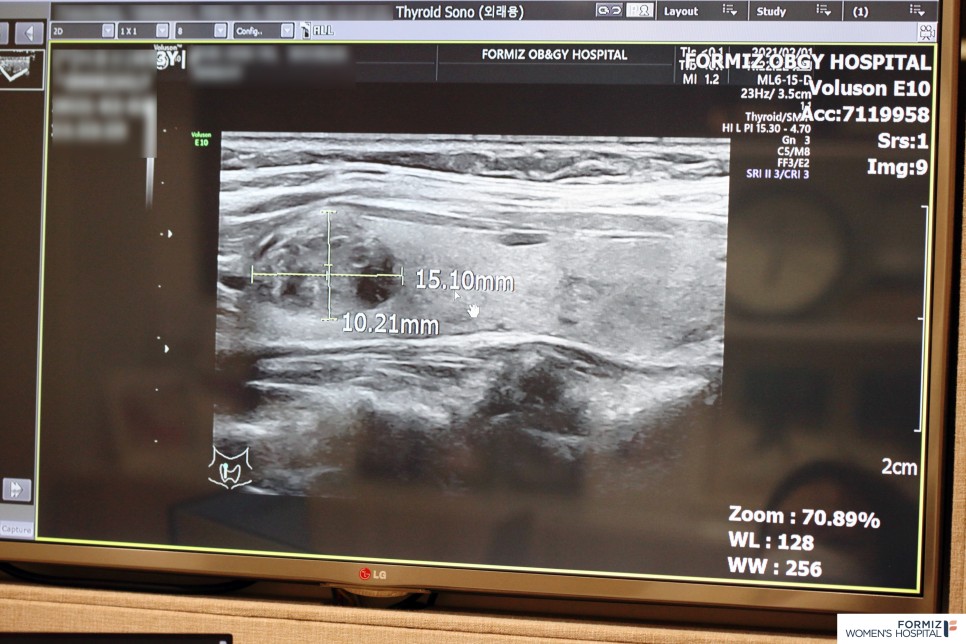

하지만 갑상선 질환의 목이나 거의 양성의 성질을 가지고 있습니다. 따라서 갑상선류가 생겼다고 해서 무조건 제거하지는 않습니다. 그러나 양성인지 악성인지를 판별해야 하며, 1차적으로 초음파 검사로 진단합니다. 먼저 양성일 가능성이 높은 목에 덩어리가 있는 경우, 그 크기가 2㎝ 이상일 때 조직 검사를 합니다. 악성에 가깝거나 애매한, 혹은 1cm보다 클 때 조직검사를 하고, 그 형태가 악성으로 판단되는 갑상선 또는 5mm보다 클 때 조직검사를 합니다. 갑상선은 우리 몸의 보일러라고도 불리며, 그 형태에서 방패라고도 불립니다. 크기 자체는 크지 않지만 면역이나 대사에 큰 영향을 미치기 때문입니다. 나이가 들수록 그 기능이 약해지는 것도 큰 고민입니다. 스트레스, 과로, 무리한 다이어트에도 약합니다. 그래서인지 남성보다 여성에게 더 쉽게 발병할 수 있는 질병입니다. 우리는 종종 갑상선 기능 이상이나 갑상선 의심 갑상선암 등의 이유로 활동을 중단한 연예인의 소식을 듣곤 하는데 그때마다 ‘인생은 정말 모른다’는 실체 없는 불안감을 느끼기도 합니다.

포미즈에서는 초음파로 갑상선류의 악성/양성 여부를 정확히 진단하고 단순 물집의 경우에는 주사를 이용하여 주기적으로 물을 빼는 치료를 합니다. 만약 조직 검사상 양성이면서 치료를 요하는 증상이 있는 경우에 갑상선 고주파 절제술을 실시합니다. 갑상선 고주파 치료는 고주파 열을 방출하는 바늘을 이용하여 갑상선류를 열을 이용하여 제거하는 치료 방법입니다. 고주파 치료는 흉터가 없고 회복이 빠르다는 장점이 있습니다. 건강을 지키는 방법은 어쩌면 아주 가까운 곳에 있어요. 포미즈 여성병원에서 갑상선 질환 상담으로 건강한 생활을 하시기 바랍니다.